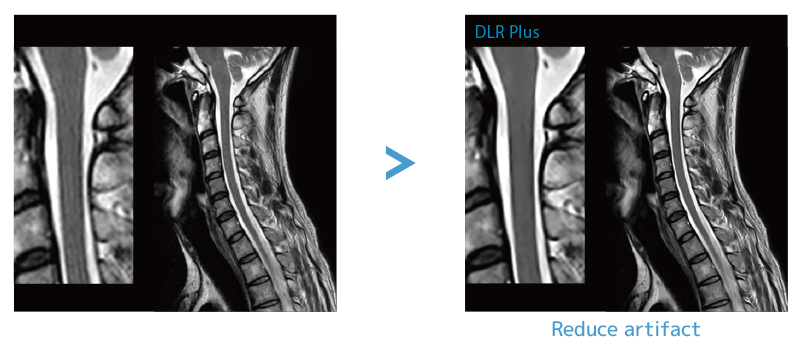

IP-RAPID, which enables shortened scan time while maintaining image quality, and DLR Plus, which improves the image quality by using Deep Learning technology*8.

By combining these two technologies, easy-to-diagnose images can be scanned with fast scan speed.

SNR and sharpness can be improved by post-reconstructing

Improving SNR and reducing wrap-around artifact through post reconstruction.

Deep Learning technology*8 enables image quality adjustment after imaging is complete. It optimize SNR and improve image sharpness by processing MRI signals in stages (k-space signal processing).

This brings super-resolution and reduces truncation artifacts.